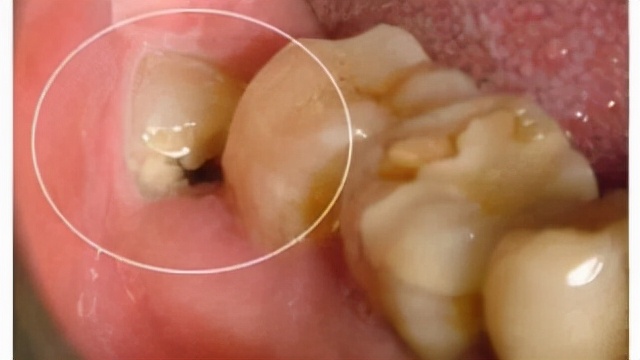

某一天你照镜子,不经意间发现自己的牙齿有了小黑点或者小黑线。于是你用牙刷,刷了几次,可是怎么也刷不走它,慢慢地就放弃了。

一个小小的黑点,在黑点之下的内部却大有乾坤。

如果龋齿是黑色的,只有小黑点或者小黑线,且这个龋齿存在很久一直不影响生活,这个龋就是慢性龋或者静止龋。

浅龋:牙齿表面有黑点或者黑线,日常饮食作息都不会出现疼痛现象,龋坏只破坏了牙釉质。